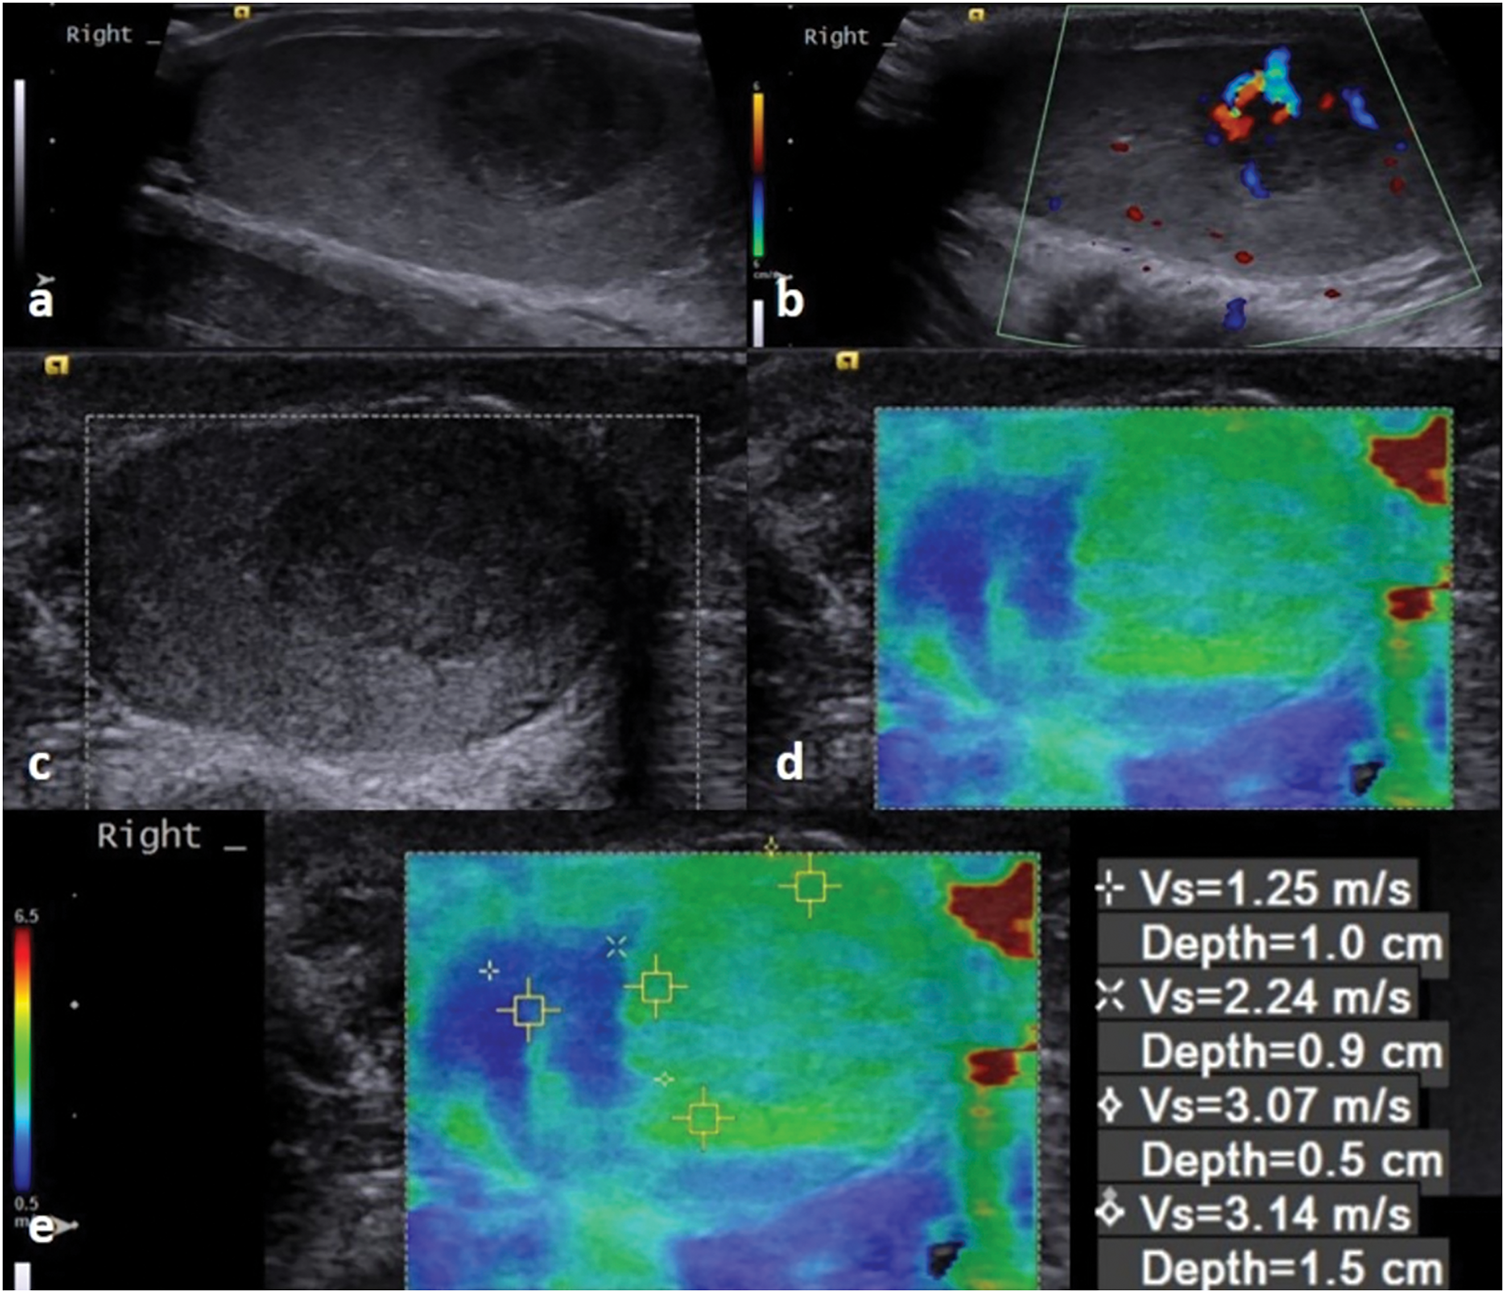

FIGURE 1. Ultrasound images of a 28-year-old patient with a pathology report indicating seminoma. (a) There is a 10 mm hypoechoic solid lesion that can be seen in the B-mode image. (b) In the Doppler image, there is a presence of vascularity. (c,d) A qualitative elastography image shows a hard lesion compared to the testicular parenchyma. (e) In the quantitative elastography images, the results of measurements taken from various depths of the lesion can be seen

During the testicular ultrasound, the patients lie in the supine position. Patients are instructed to position the penis superiorly, and draping is used for privacy. Patients are primarily evaluated by gray scale (B-mode) examination. The echogenicity of the lesion relative to the testicular tissue, edge characteristics, presence of calcifications and cystic areas, and dimensions are described in detail in the report. The longest dimensions are specified in all three axes (TR × AP × CC). Blood supply is evaluated with color Doppler ultrasound. Elastography examination is performed in cases with difficulty in diagnosis, and stiffness rates are calculated compared to normal testicular tissue (Figure 1). Testicular MRI imaging is recommended for patients who still cannot reach a result (Figure 2).